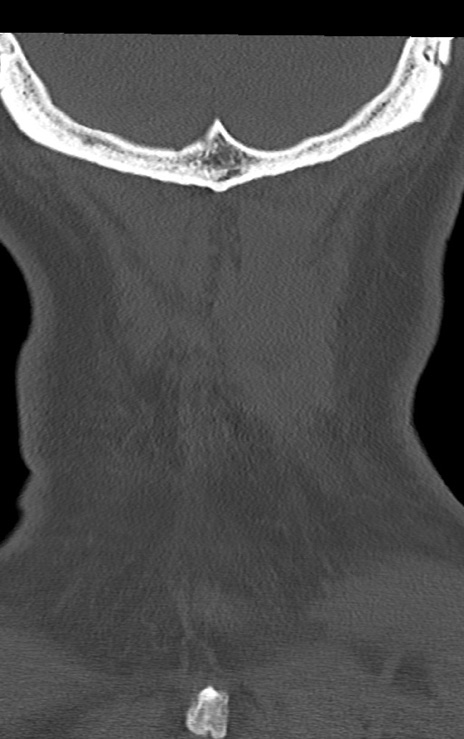

頚椎CT

矢状断像